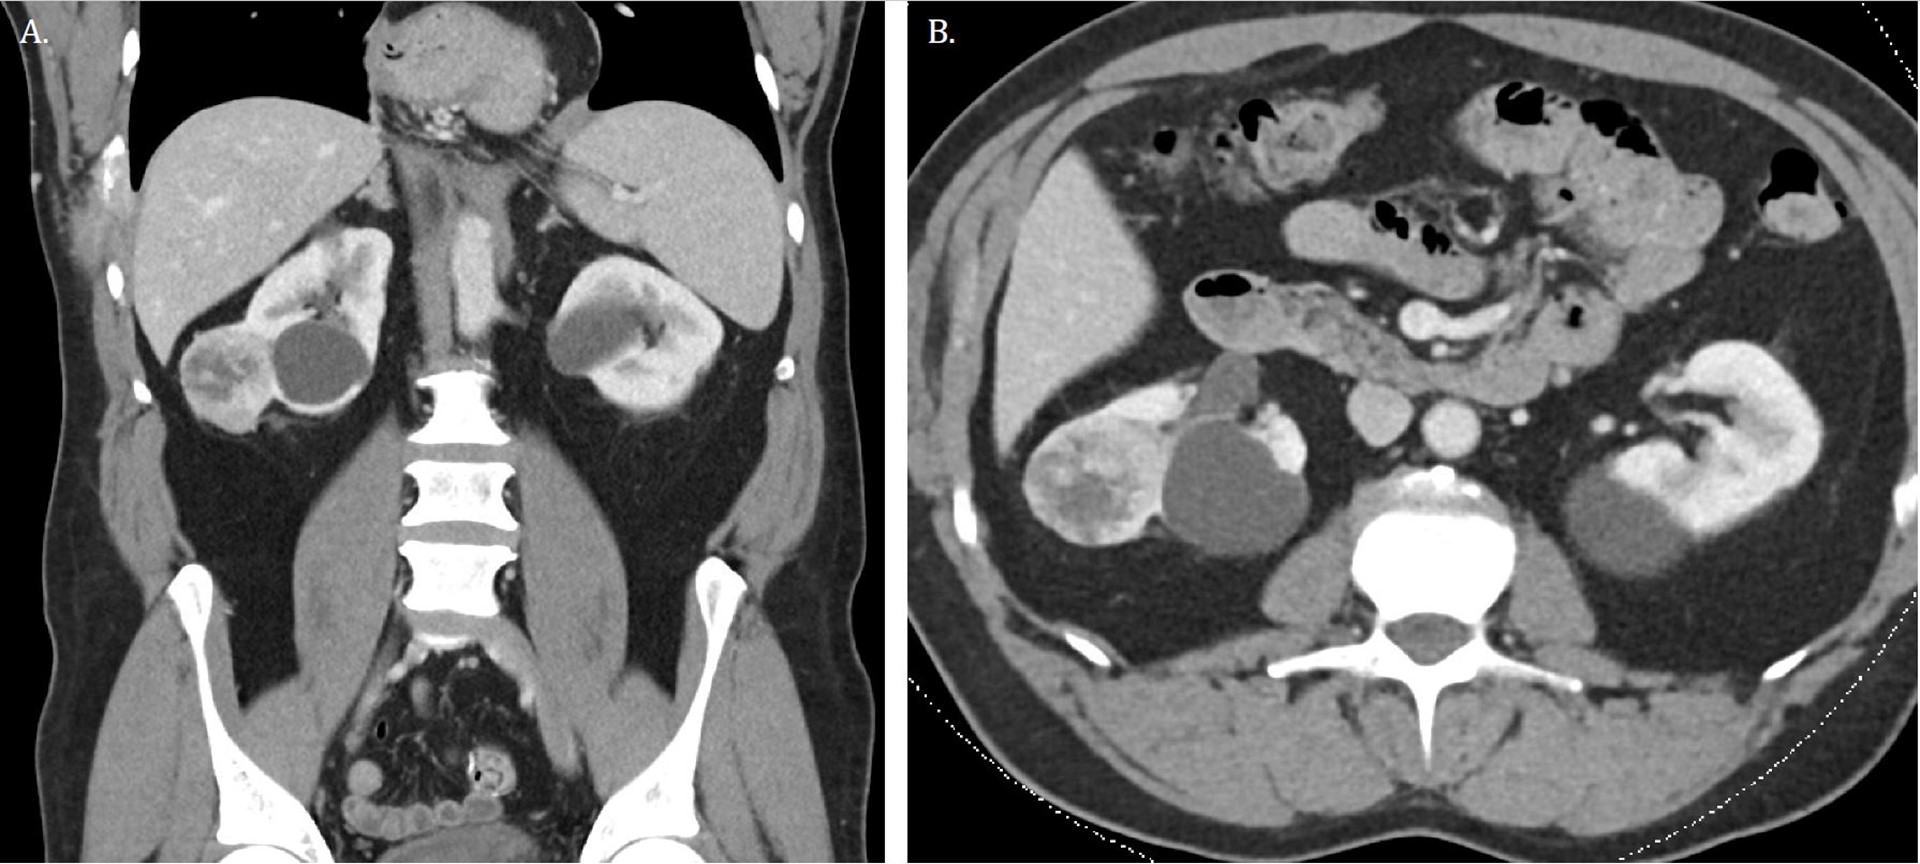

Work-up of the right chest wall mass included a CT chest which demonstrated an expansile destructive right rib lesion measuring 5.8 x 4.1 x 6.5 cm and a nonspecific 3mm pulmonary nodule (Figure 1). A CT-guided biopsy of the chest wall mass was most consistent with clear cell RCC (Figure 3). Subsequent CT of his abdomen demonstrated a 3.9 x 4.2 x 4.0 cm heterogenous exophytic right renal mass (Figure 2). The patient denied gross hematuria, unintentional weight loss, constitutional symptoms, and pain. His physical exam was remarkable for a palpably firm right chest wall mass, and lab data revealed normal serum hemoglobin, absolute neutrophil count, platelets, and calcium. With his excellent performance status and normal lab results he was assigned to the intermediate risk group as per the International Metastatic RCC Database Consortium (IMDC) prognostic model13. Notably, he had mild baseline chronic kidney disease with a serum creatinine of 1.5 and an estimated glomerular filtration rate was 48.2 ml/ min/1.78 m2.